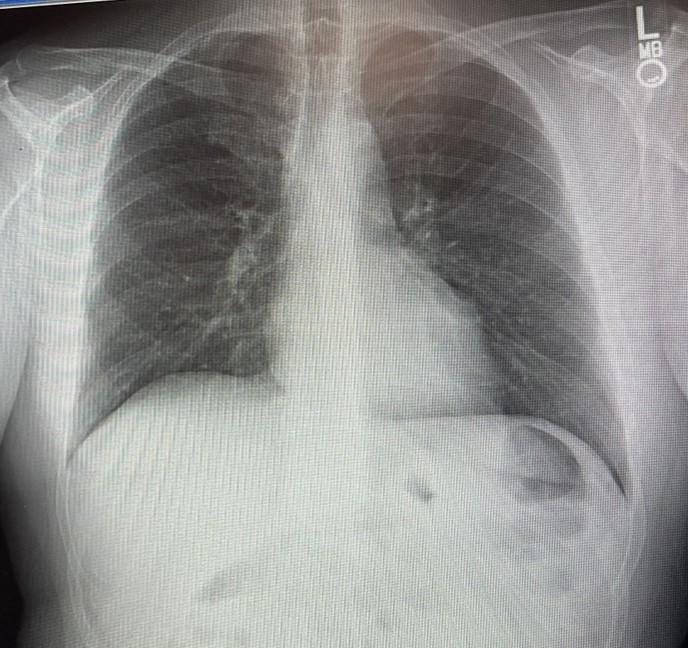

A PA of the chest shows RLL infiltrates (left image). A CT scan of the chest confirms the presence of RLL infiltrates (right image).